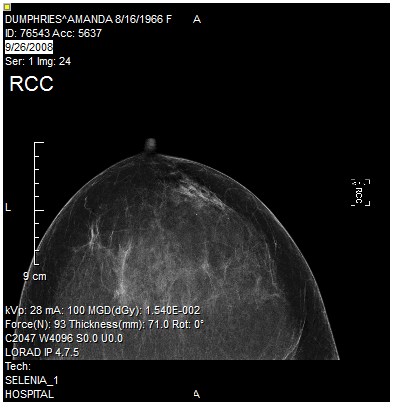

The Rotate Image 90 Degrees Clockwise tool will rotate an image 90 degrees to the right. The following example illustrates an image before and after the Rotate Image 90 Degrees Clockwise tool is applied.

Before